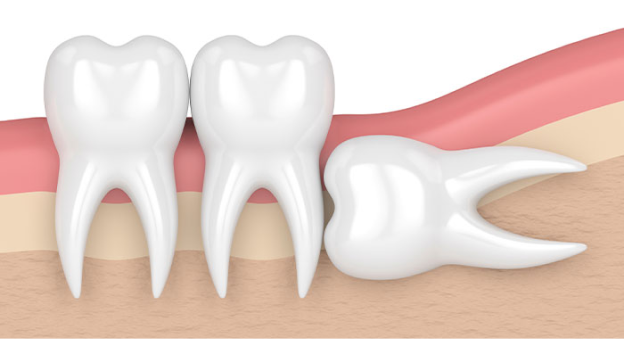

• 사랑니 발치 이유 4

옆으로 누워서 자란 사랑니

사랑니가 누워서 자라면 바로 앞쪽 어금니 뿌리를 압박해 염증 등의 문제를 일으키거나 앞쪽 어금니와의 사이에 음식물이 잘 끼게 되어 충치와 염증을 유발할 수 있습니다.